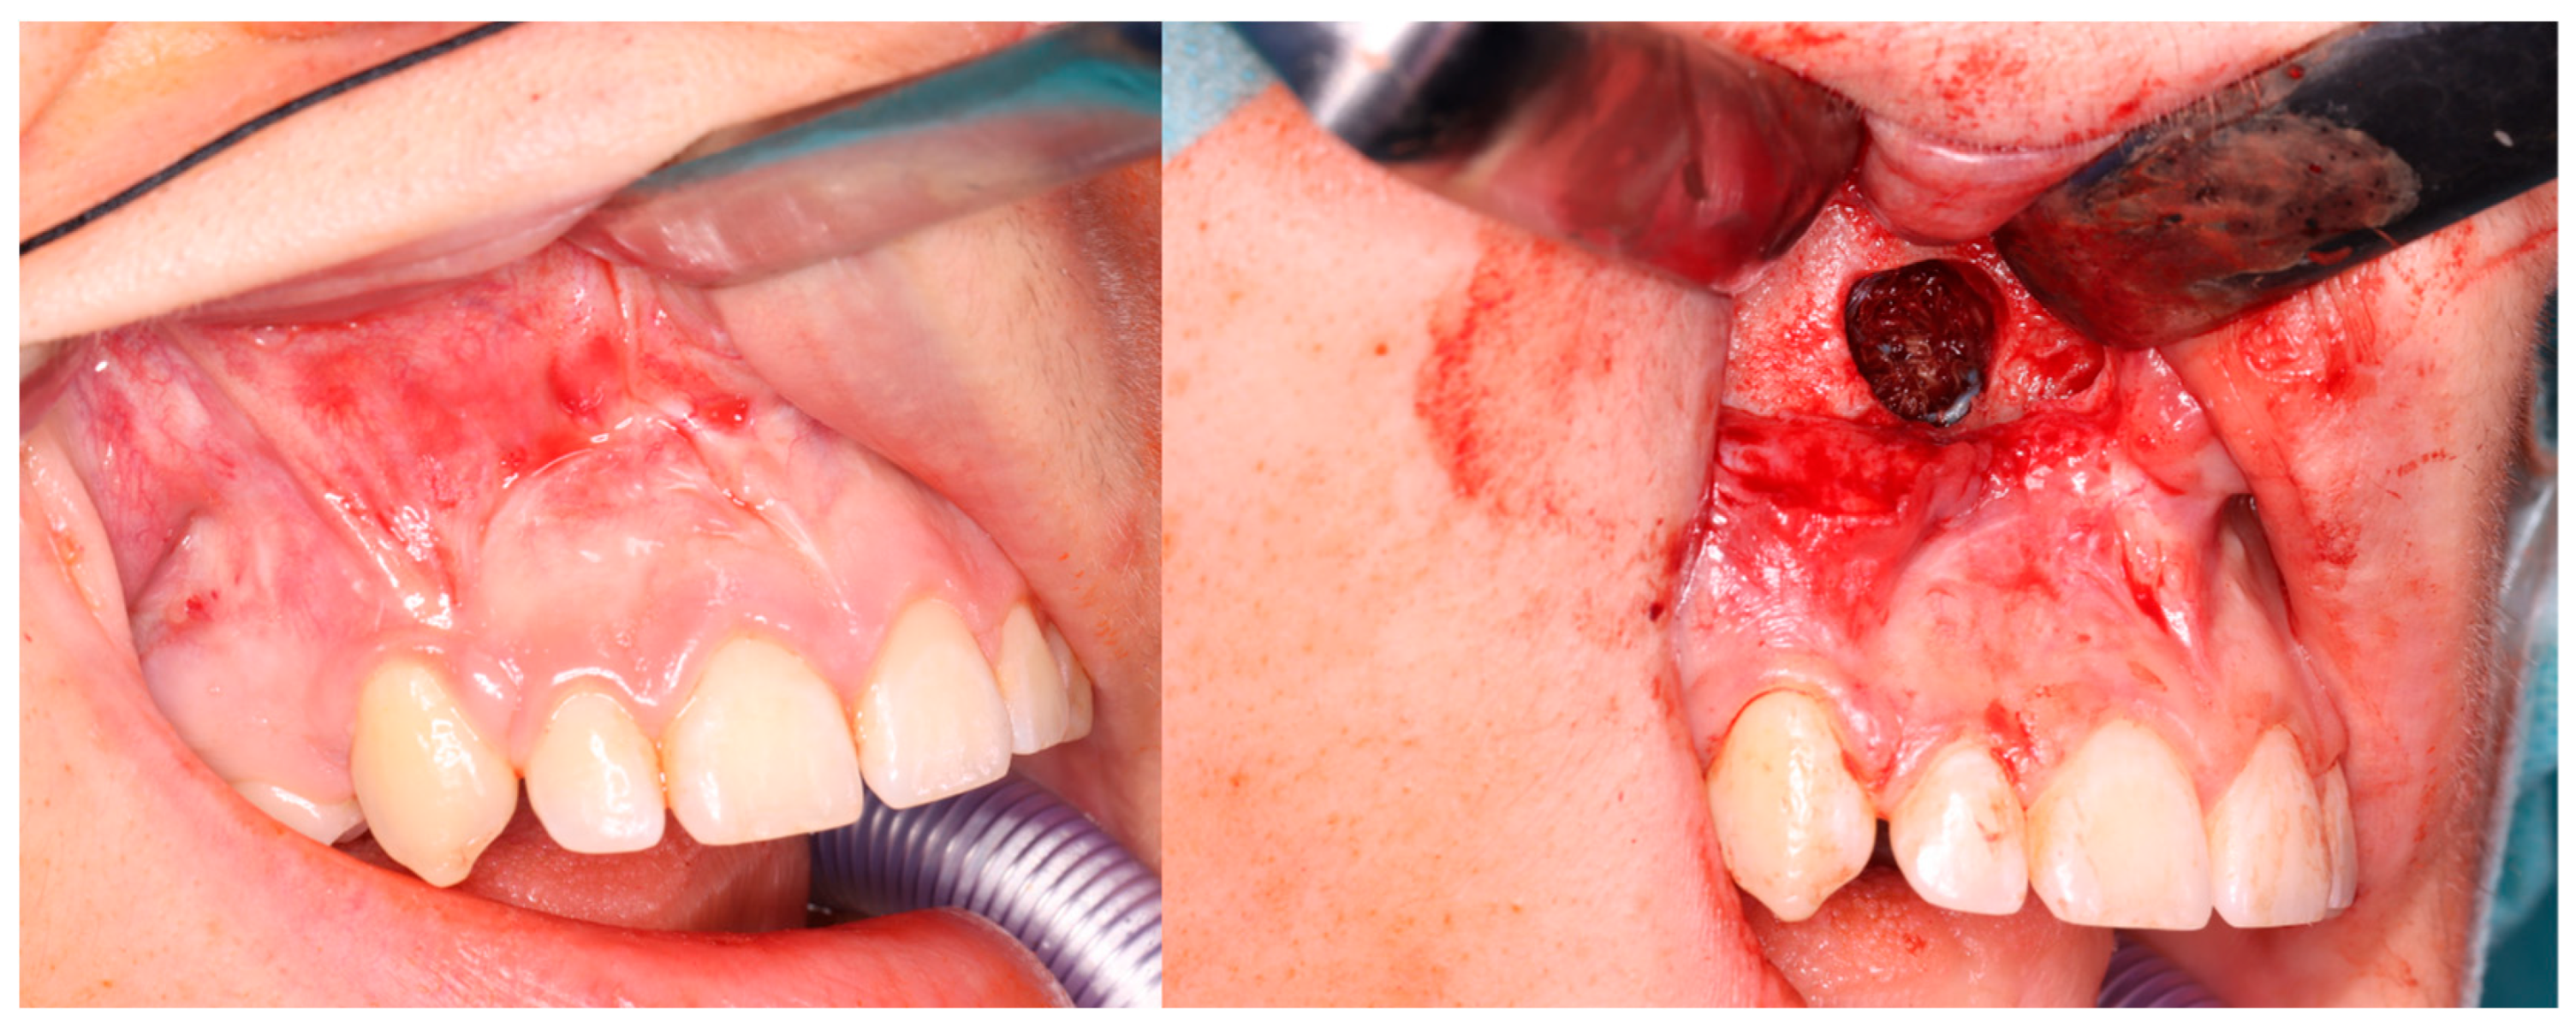

1. Introduction

3. Results

3.4. Complications During Treatment

3.5. Recurrence